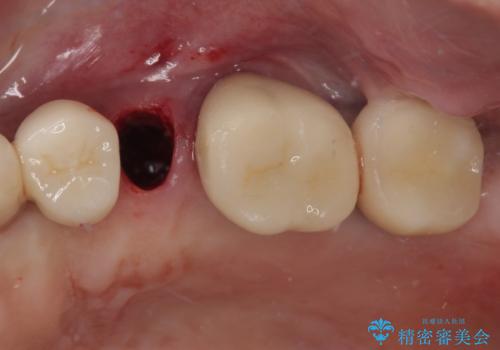

- 奥歯に装着していたクラウンが外れてしまったとのことで来院された患者様です。

診察したところ、歯根に破折線が確認され抜歯が必要な状態でした。

歯肉や歯槽骨の状態は良好であったため、抜歯即時埋入インプラントによる補綴治療を行うこととしました。